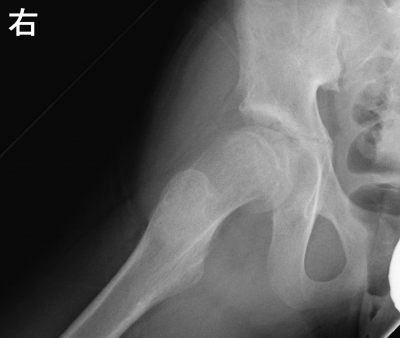

12 歳の女児。右大腿部から膝の痛みを主訴に来院した。1か月前に友人とぶつかって転倒した後から、痛みが出現した。様子をみていたが痛みが軽快しないため受診した。身長 148 cm、体重 50 kg。体温 36.3 ℃。右股関節前方に圧痛を認める。 歩行は疼痛のため困難である。右股関節可動域は屈曲と内旋とに制限がある。血液生化学所見に異常を認めない。股関節のエックス線写真を示す。

初期対応として適切なのはどれか。